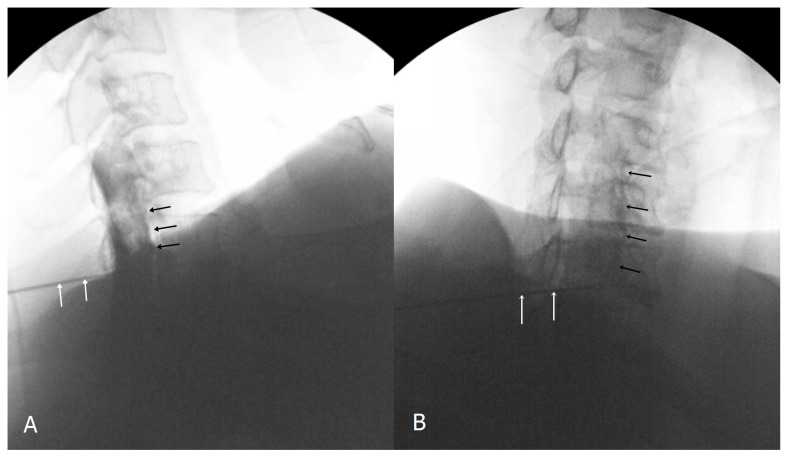

Cervical interlaminar epidural injection: lateral view (A) and contralateral oblique view (B) showing ventral epidural contrast spread. White arrows indicate the Tuohy needle position.